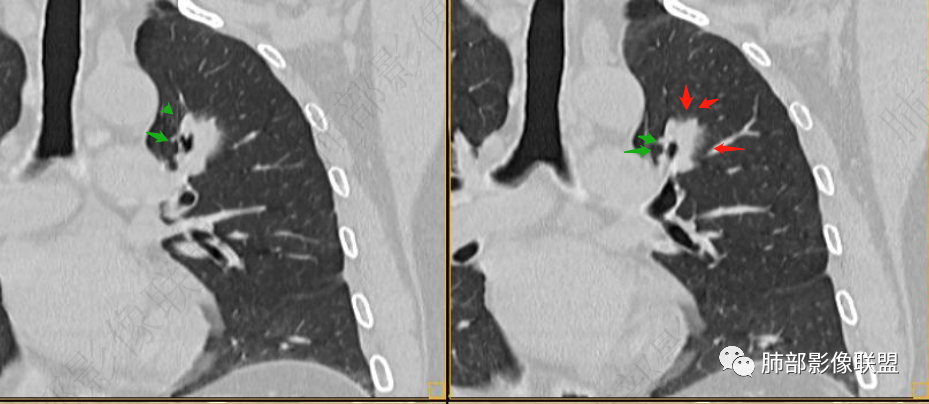

男性,肺结节3年,发现逐渐增大,影像表现,左肺舌段结节,边缘可见磨玻璃密度影,内部走形下舌段支气管变窄,增强呈持续强化,首先考虑肺腺癌,鉴别炎性肉芽肿,真菌/隐球菌。

中老年男性,发现结节,影像表现,左肺上叶结节,实性部分有膨胀性生长,边缘可见磨玻璃影,似清晰似不清晰,病灶与支气管关系密切,部分支气管似狭窄及僵硬,增强病灶强化明显,考虑腺癌(粘液性腺癌)鉴别炎性肉芽肿。

左肺上叶尖段支气管旁结节伴磨玻璃影,磨玻璃影边缘模糊,支气管走形正常,病变无明显分叶及毛刺,收缩不明显,增强呈延迟高强化。先考虑炎性肉芽肿。肿瘤待排。

左肺上叶支气管旁结节伴磨玻璃影,磨玻璃边缘略模糊,沿支气管走行,明显不均匀延迟强化,3年逐渐增大,考虑腺癌,鉴别淋巴增殖病变,炎性肉芽肿

中年男性,查体发现,左肺上叶靠近支气管旁实性结节,周围有磨玻璃影,边界清,密度高,明显强化,三年缓慢进展,考虑腺癌,鉴别类癌或炎性肉芽肿。

初始病灶应该是这里

病灶朝前、外侧进展

病灶包括两部分

1、实性2、周围GGO

目前看支气管通畅